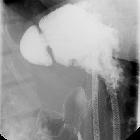

Fluoroscopy

A well defined saccular collection of barium sulfate contrast outpouching from the gastric wall.